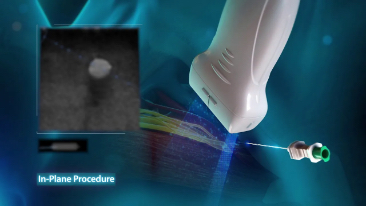

Dank der ZONE Sonography?-Technologie (ZST+) wird das B-Bild des Resona 7 ├╝ber die komplette Tiefe fokussiert, sodass keine Fokuspunkte mehr gesetzt werden m├╝ssen. Die Schall-Lauf-Geschwindigkeit (SSC) wird auf Knopfdruck individuell auf den Patienten angepasst, was die Darstellung von Organen, Grenzfl?chen und Gewebever?nderungen erheblich verbessert. Und dank der fortschrittlichen iFusion-Funktion k?nnen optional die Daten von Ultraschall-, MRT-und CT-Bildern synchronisiert werden.